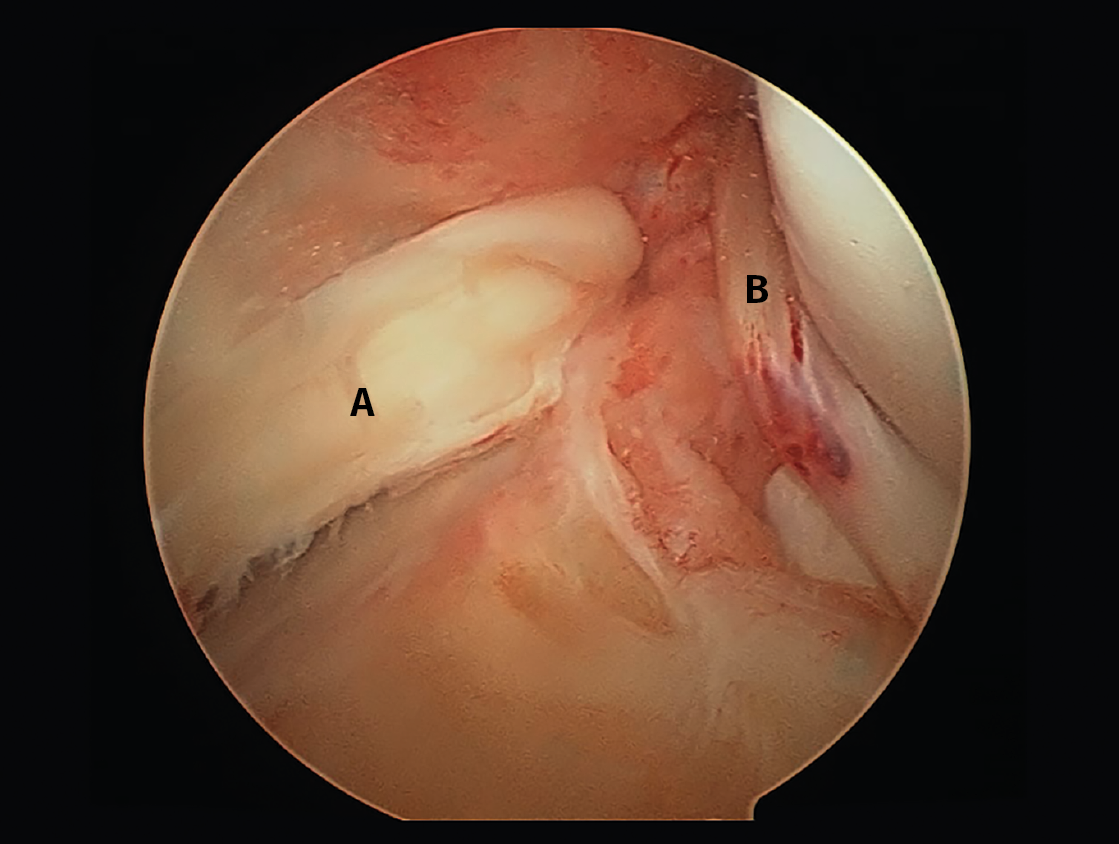

Observamos una doble rotura de ambos meniscos luxados en asa de cubo tras un traumatismo deportivo en una rodilla izquierda. En pacientes jóvenes, este tipo de roturas meniscales se deben intentar reparar. A: asa de cubo de menisco interno; B: asa de cubo de menisco externo.